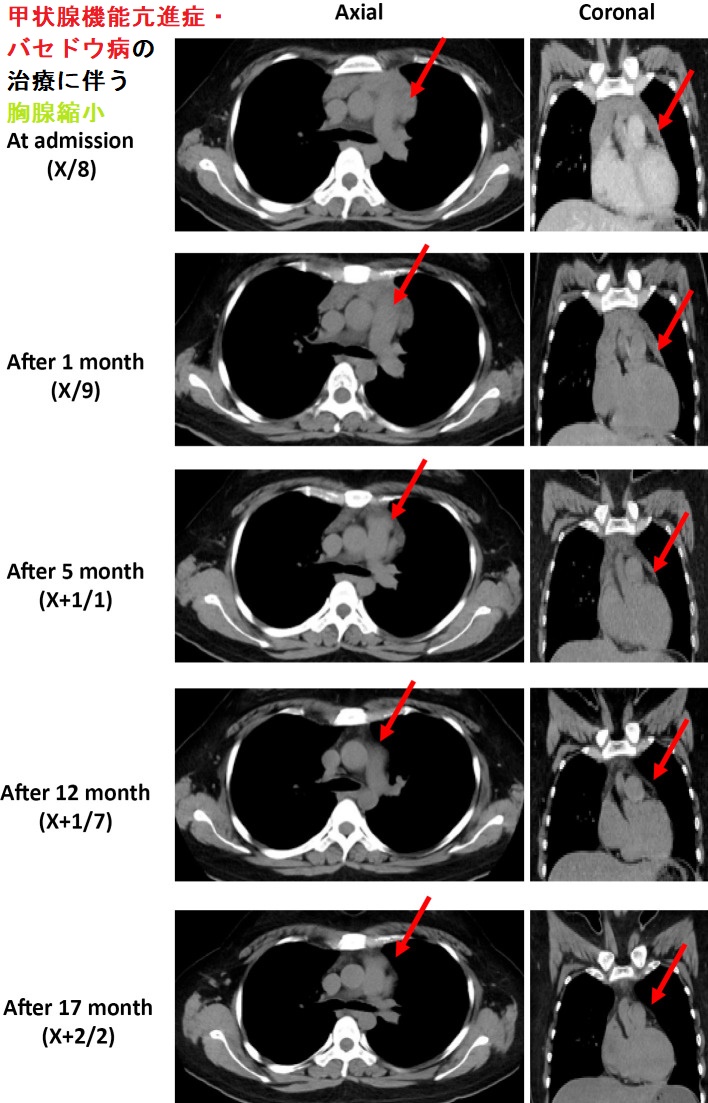

治療により甲状腺機能が正常化すると胸腺過形成も縮小する症例が数多くあります。筆者が調べたところ、

- 19-52歳の女性

- 胸腺は6×20mm~18×52mm~75×100mmと様々だが、かなり大きい

- 甲状腺機能亢進症/バセドウ病の治療開始後3-9カ月して胸腺は縮小傾向、全症例が消失する訳で無く、15カ月で消失する症例もある

[Intern Med. 2022 Sep 15;61(18):2753-2757.][J Endocrinol Invest. 2014 Dec;37(12):1175-9.](日呼外会誌 24(1),2010,69-73)(日呼外会誌 21(1),2007,43-47)(第56回 日本甲状腺学会 P1-100 抗甲状腺薬治療に伴う前縦隔腫瘍の縮小経過を追跡し得たバセドウ病の2 例)